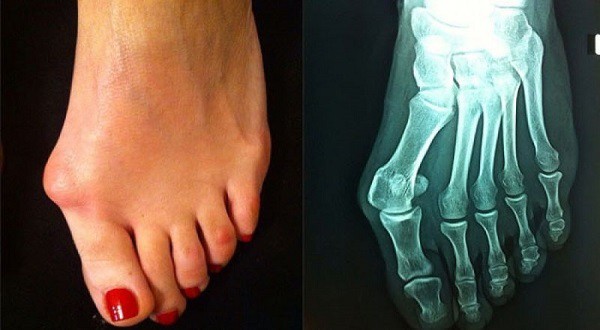

What to do about bunions?

People who have problems with bunions are thrilled with the summer when they can wear open shoes. As autumn arrives  this problem becomes much more unpleasant.

A guest at the National TV, specialist in orthopedics with traumatology of Atlas General Hospital – Dr. Jovo Stojsavljević talked about the problem of the bunions, the method of treatment and the period of recovery after the operation of this problem.

Cause of bunions is first of all excessive load in non natural position. Inherited elements also influence bunions phenomenon, especially in women, because it is 15 times more common in women than in men. Wearing high heels influence the soft structures of joints inside the foot, not only muscles but fascia, tendons, ligaments become more loose and thus the front part of foot are widened and flattened. In the same time the arches of foot are lowered and also longitudinal arch of the foot. When the arch of the foot is flattened, then metatarsal bones are widened which brings coupling of adductor musculature of a thumb to dragging fingers toward each other.

When bunion is already formed then the only permanent solution is operation. All other methods and aids that one can find on the internet, newspapers and entertainment magazines are only temporary aids which can eventually ease the pain for short time (several months maybe a year), but it can not cure bunions. There are insoles that can help by lifting medial arch of the foot; one can use personalized insoles for best results. It can be done for each foot individually, so metatarsal bone can be lifted. Insoles lift that part of the foot so the support can be brought back to physiological points, and the results can be more durable.